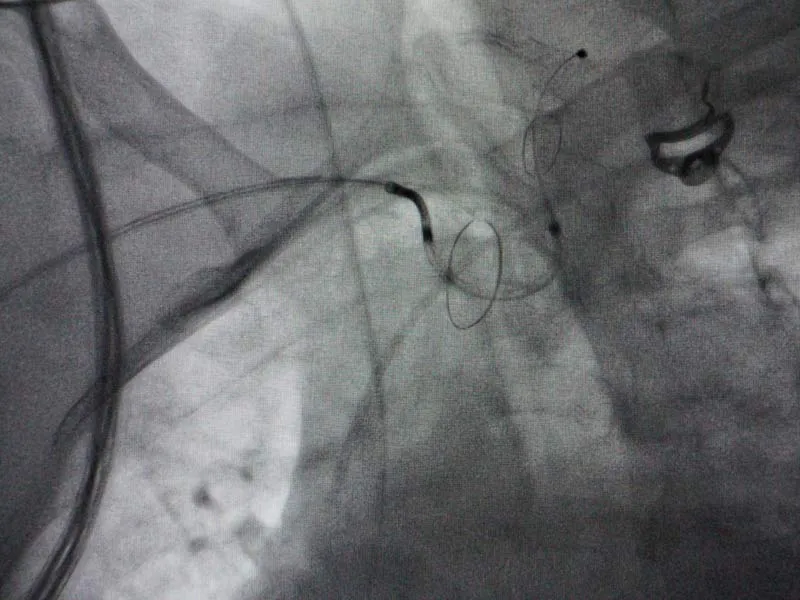

El dispositivo llamado SentinelTM, contiene dos paraguas que se colocan, a través de un catéter, en las arterias carótidas que son el principal suministro de sangre al cerebro.

Estos paraguas capturan todo el material que puede desprenderse durante procedimientos como TAVI, evitando que lleguen al cerebro.

El dispositivo de protección embolica cerebral, fue utilizado recientemente con éxito en el Hospital Zambrano Hellion, durante un procedimiento TAVI en una paciente de alrededor de 70 años.